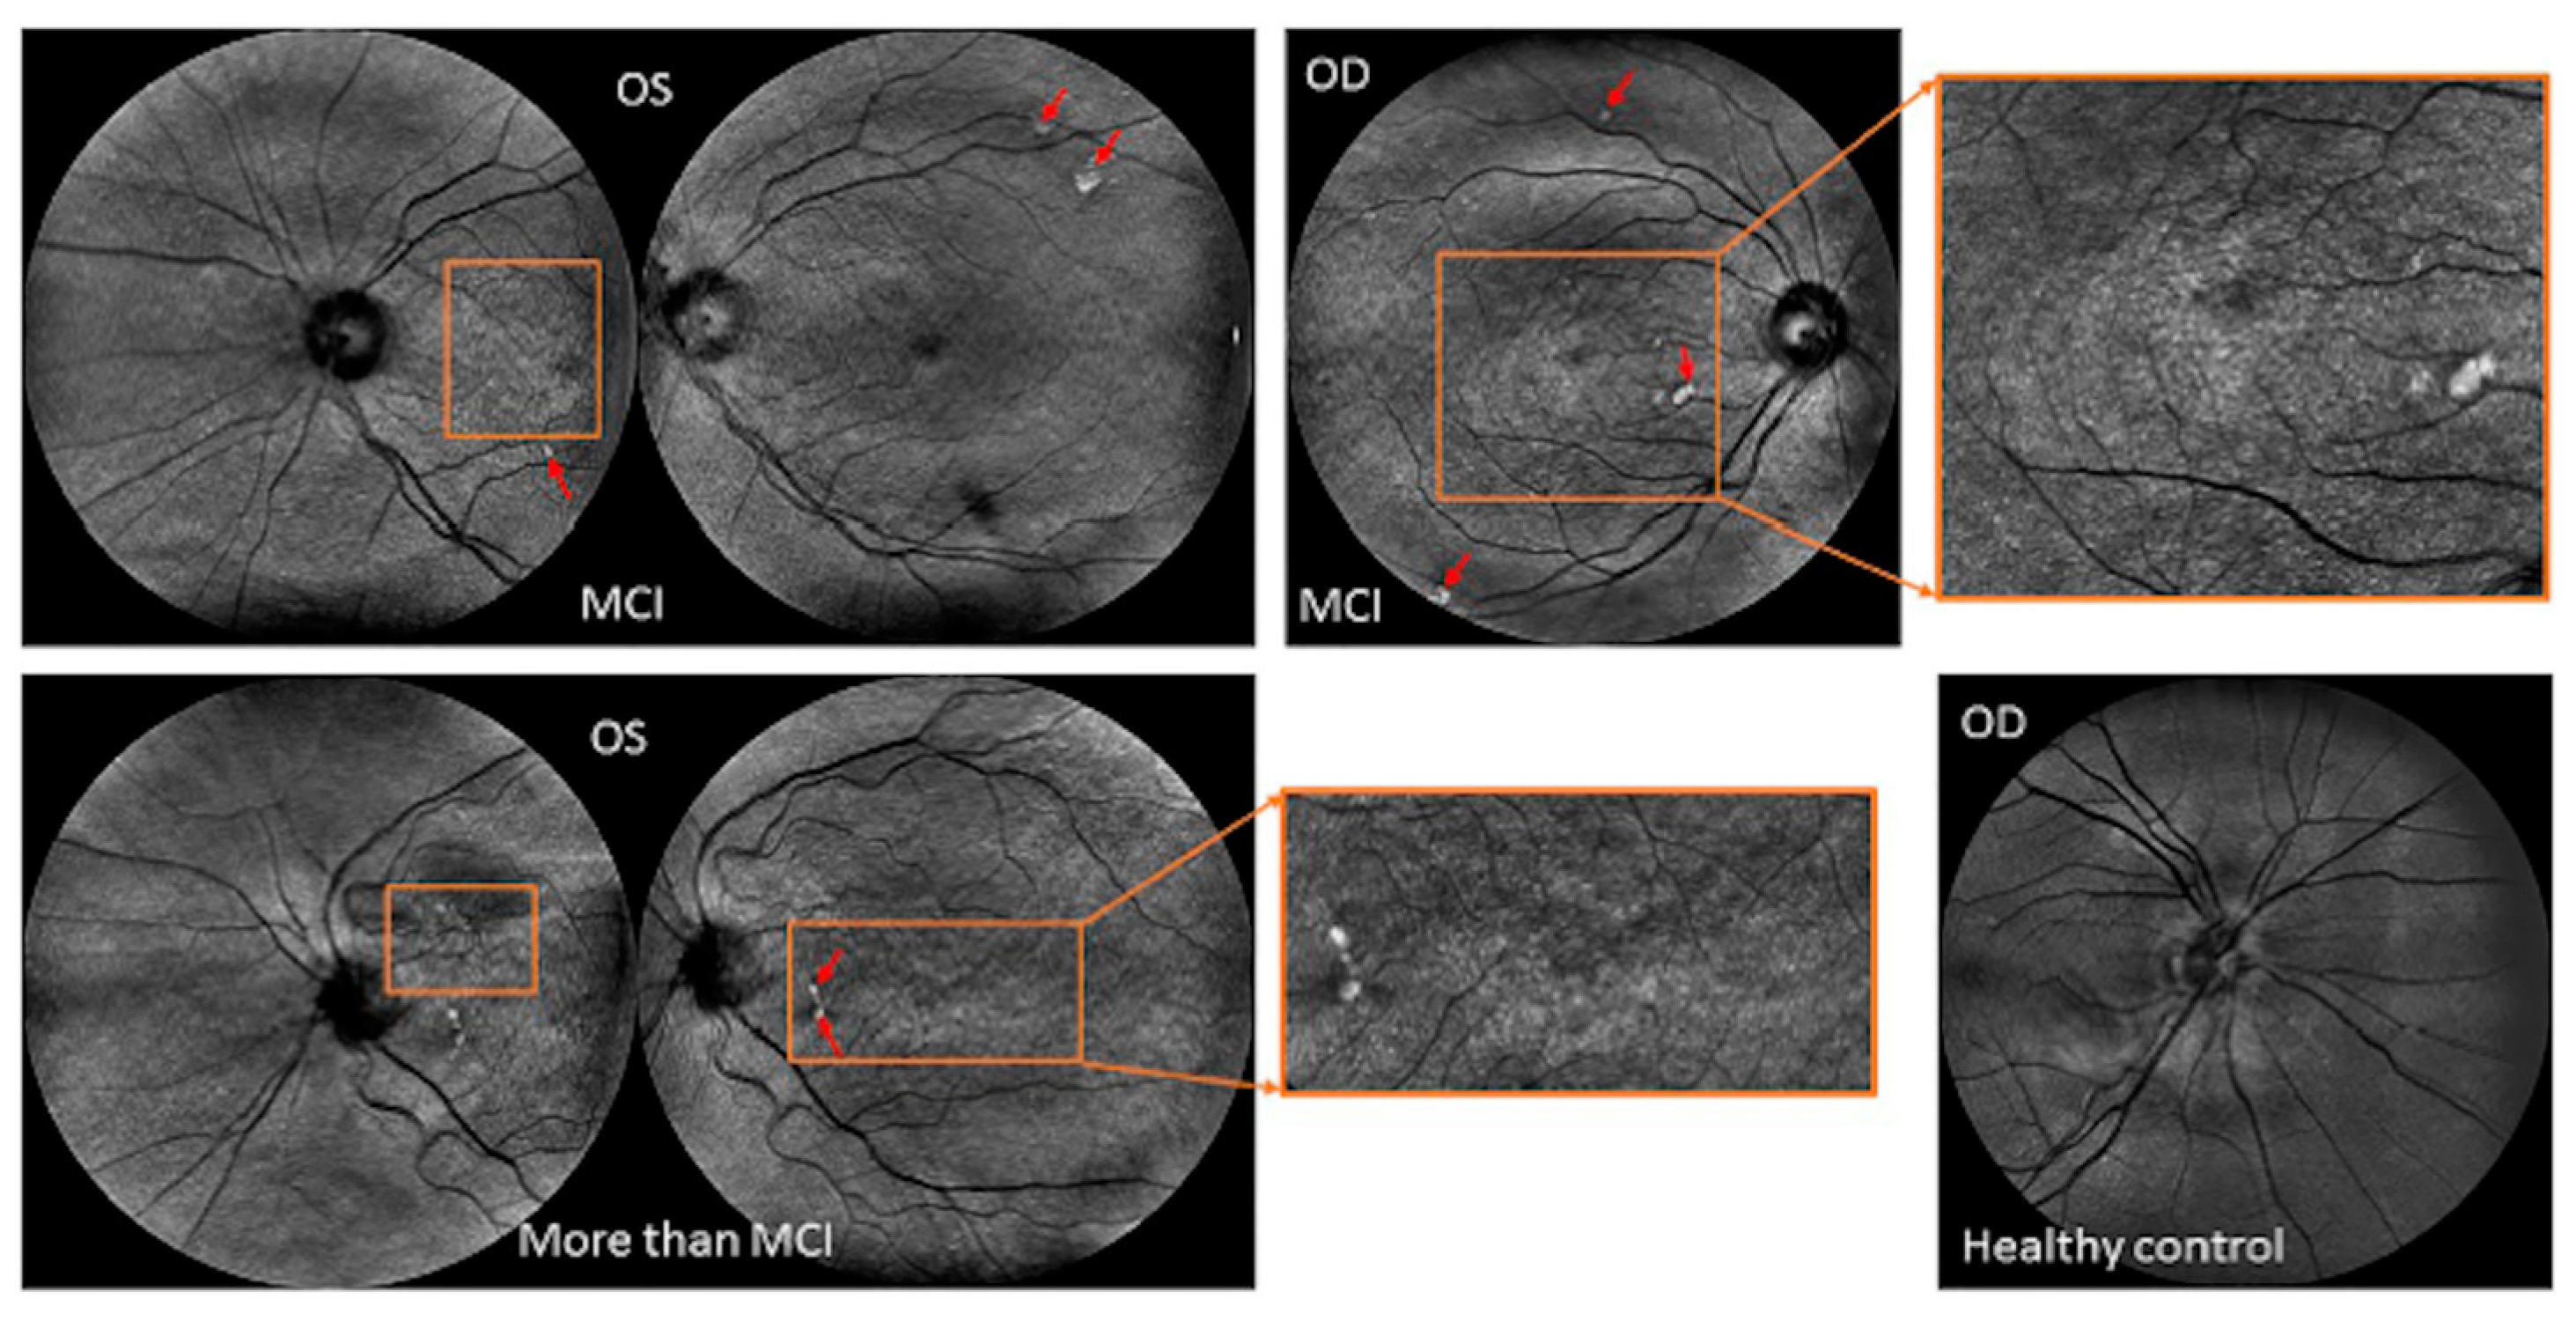

3.4. OCT Findings and AD Biomarkers

3.5. OCT Findings in Relation to Advanced Imaging and Electrophysiological Techniques